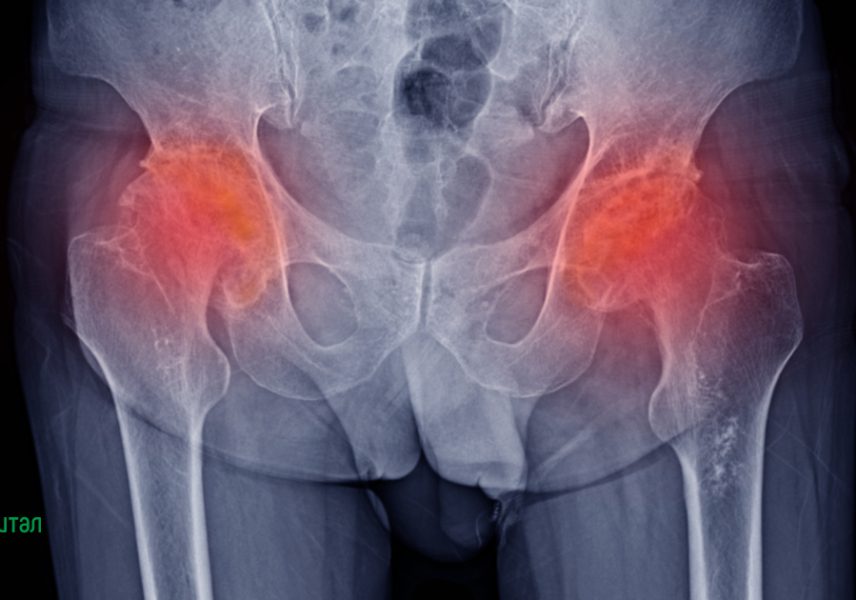

Асептична некроза на тазобедрени стави е проблем, който е нерядко срещан и затова заболяването бе разгледано от професор Христо Деянов в предаването „Академия Здравитал“. В своята лекция водещият акцентира върху причините, клиничната симптоматика и лечението, свързани с болестта. Здравословното неразположение може да засегне хора от всякаква възраст, мъжете са по-уязвими. Когато са диагностицирани деца, в медицината е общоприето названието „Болест на Пертес“, а при по-възрастни пациенти – „Болест на Чандлър“.

Заболяването представлява постепенна некроза, загуба на плътност и структура в главичката на тазобедрената става. В повечето случаи причините за състоянието остават неизяснени. Съществуват становища, че при децата предразполагащ фактор са генетичната обремененост и някой слабо изяснени метаболитни нарушения. Откриването на симптоматика при Болест на Пертес изисква веднага консултация с детски ортопед, за да бъде определен стадия на състоянието и лечението – терапията може да варира от режим и модел на двигателно поведение до оперативни интервенции (това е радикално решение). Медикаментозната консервативна терапия като единствен метод рядко води до положителен изход за асептична некроза на тазобедрени стави.

При първи стадий има незасегната здрава бедрена кост, бедрена главичка и в един момент настъпва исхемия, започват некротични изменения. Във втората част идва фрагментацията на разрушените костни повърхности – това е съпроводен със силна болка, нарушени движение. Третият стадий се асоциира с резорбция (преминаване) на костните части от околната здрава тъкан – в този момент има „заблуждаващо“ подобрение, а всъщност проблемът еволюира.

Четвъртият етап е свързан с реваскуларизация, заради възстановителните сили на организма. Говорим за непълен и некачествен процес, тъй като само в някой участъци се подобрява кръвоснабдяването. Крайният момент на заболяването е ставната деформация, скъсяването на крака и увеличеният физически дискомфорт. Ако не се вземат необходимите мерки, в рамките на няколко години пациентът може да стигне до инвалидизация.